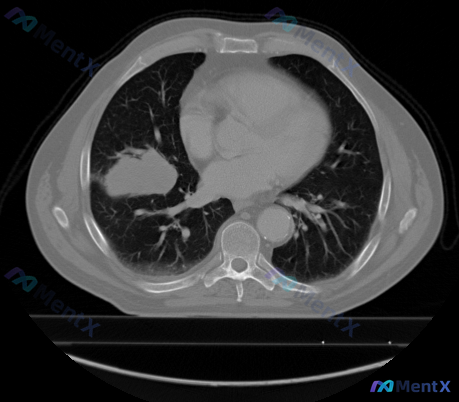

整理了一份最近看到的胸部CT病例,影像表现有点「迷惑性」,特意把分析思路理清楚分享出来,避免踩坑。 --- 先看核心影像表现 - 部位:右肺中叶,靠近心缘 - 病灶性质:类圆形实性肿块,肉眼估测约3-4cm - 关键细节: ✅ 边界相对清晰 ✅ 边缘可见浅分叶,但无明显粗糙毛刺 ✅ 无明确胸膜牵拉征...